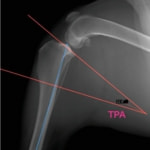

TPLO

TPLOはSlocumが提唱した前十字靭帯断裂に対する手術法であり、脛骨高平部を水平に回転させる骨きり術によって、体重負重時の脛骨の前方変位を抑制し、膝関節を安定化します。犬の脛骨高平部の角度(Tibial plateau angle:TPA)は約25°と言われており、この角度を約6.5°に矯正すると脛骨の前方変位が抑えられ、膝関節が安定します。世界的にも手術成績が安定している術式です。

本症例は、走った後に左後肢を挙上していることを主訴に来院されました。触診時に左膝関節のクリック音を聴取、レントゲン検査にて左脛骨の前方変位が認められました。術中に、前十字靱帯の断裂及び内側半月板の損傷、内側の軟部組織の顕著な腫脹を確認。半月板切除、TPLOを実施しました。周囲組織への炎症の波及もあったため回復に時間を要しておりますが、徐々に跛行頻度は減少傾向にあり、現在も経過観察中です。術前に約29°あったTPAは術後に約10°まで矯正されました。

手術前後のTPA(脛骨高平部の角度)を測定しています。

約29°から約10°へ矯正されています。